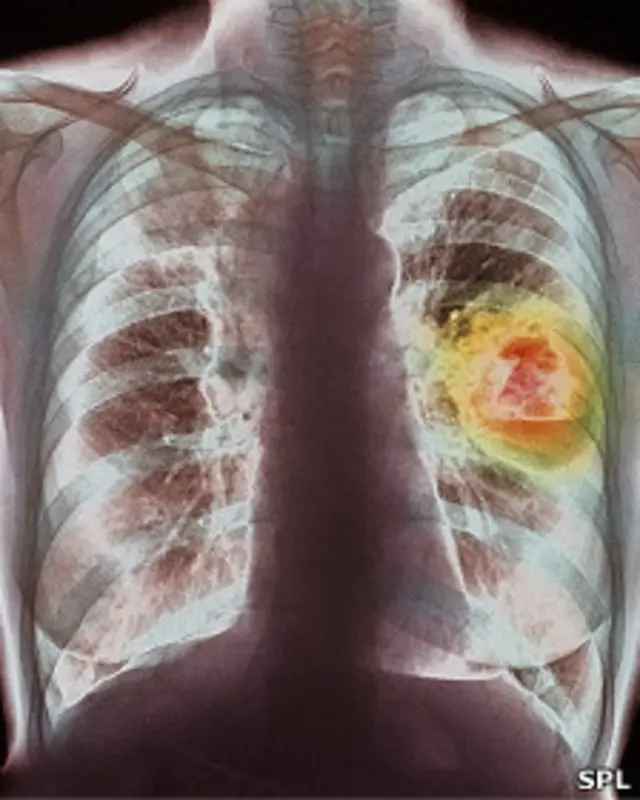

El cáncer de pulmón supera al cáncer de mama en Europa

El cáncer de pulmón superará al cáncer de mama como la principal causa de muerte por cáncer entre las mujeres en Europa en los próximos años, según expertos.